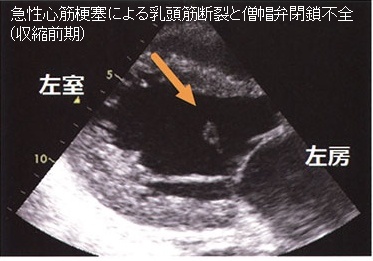

心筋梗塞(右冠状動脈、回旋枝梗塞)による乳頭筋断裂→急性の僧帽弁閉鎖不全(MR)と急性左心不全

甲状腺機能亢進症/バセドウ病、甲状腺機能低下症/橋本病では僧帽弁腱索/乳頭筋断裂の頻度が高い(Endocr Rev. 2005;26(5):704–728.)。

特に循環血液量・心拍出量が増加する甲状腺機能亢進症/バセドウ病では、僧帽弁腱索/乳頭筋断裂を引きおこす危険性が高い。(J Endocr Soc. 2018 Sep 17;2(11):1246-1250.)[Endocrinol Diabetes Metab Case Rep. 2022 Jul 1;2022:22-0298.]